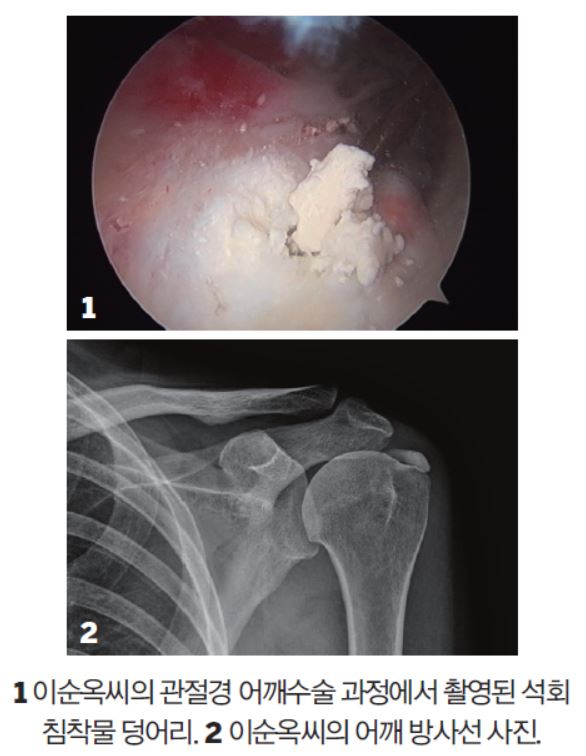

수술 과정은 그리 복잡하지 않다. 얇은 튜브 모양의 관절경이 들어갈 수 있도록 어깨의 앞, 뒤, 옆에 작은 구멍을 내 수술을 하는 방식이다. 관절경에 달린 카메라를 통해 석회물이 생성된 부위를 직접 들여다보면서 힘줄이 다치지 않도록 제거해낸다.

윤 원장은 “간혹 수술을 해도 석회물이 남는 경우가 있어요. 이순옥씨의 석회화 부위는 넓은 편이었지만 다행히 모두 제거했습니다”라고 말했다.

“아팠을 텐데 지금까지 어떻게 참으셨어요?” 윤 원장이 이씨를 만나자마자 건넨 말이다. 윤 원장은 일반 환자보다 커다란 석회덩어리를 보고 걱정이 많았다고 기억했다. 다행히 덩어리 크기에 비해 환자가 느끼는 통증은 비교적 적었다. 석회성건염은 생성기, 휴지기, 흡수기의 3단계를 거치는데, 흡수기에 접어들었을 때는 극심한 통증이 나타난다. 만약 어깨가 너무 아파 응급실을 찾을 정도라면 대부분 석회성건염일 가능성이 많다.